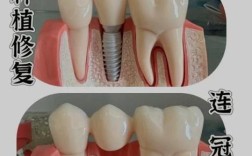

种植牙的原理是通过外科手术将纯钛种植体植入牙槽骨,与骨组织形成“骨结合”,从而支撑牙冠,牙槽骨的密度、高度、宽度是决定种植成功的关键,若患者因长期缺牙导致牙槽骨吸收(常见于缺牙时间超过3个月),可能需要进行植骨、上颌窦提升等辅助手术,增加骨量后再种植。